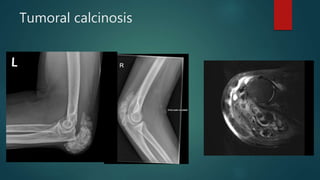

Tumoral calcinosis

• #94 "Cloud-like" calcifications in the region of the triceps insertion, olecranon, and olecranon bursa (3.3 x 7.7 x 5.7 cm). There is no connection to the underlying humerus or ulna. Bilateral extensive soft tissue calcification posterior to the elbow joint around the insertion of triceps.  US confirmed that it was extra-articular.  Limitation of extension at the elbow.